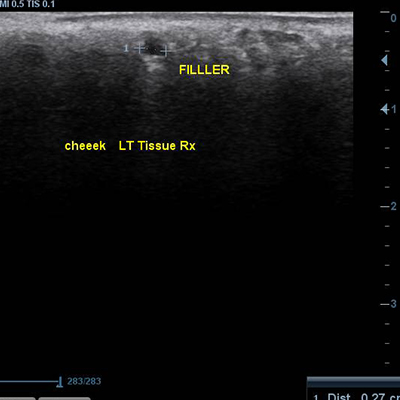

이물질제거수술

초음파검사&

이물질전후사진

[이물질제거] 17.04.04 - 이물질제거(목) - 전후사진

17.04.04 - 이물질제거(목) - 수술전후사진